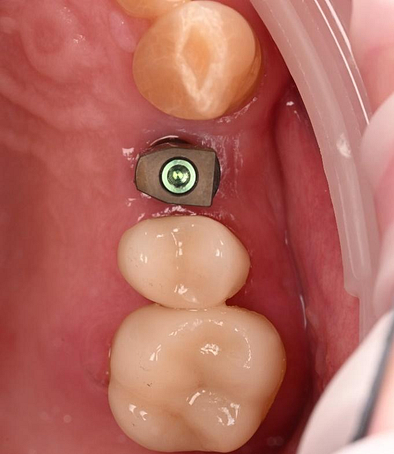

The crown was milled from a high-strength, multilayered zirconia and hand-finished to achieve a lifelike appearance.

At the final appointment, the crown was securely attached to the implant, resulting in a beautiful, natural-looking restoration.